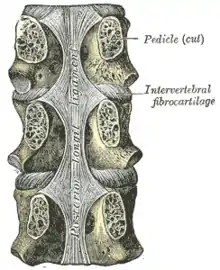

Un disque intervertébral (DIV) ou fibrocartilage intervertébral est un cartilage qualifié de fibreux, qui se trouve entre presque toutes les vertèbres de la colonne vertébrale (sauf entre C1/C2). Chaque disque est formé d'un fibro-cartilage mixte (se rapprochant d'une symphyse), et permet un faible mouvement des vertèbres. Il agit aussi comme un ligament maintenant les vertèbres ensemble. Son rôle d'amortisseur des chocs est crucial et son altération physiologique explique les nombreuses pathologies du dos.

Les disques intervertébraux sont constitués d'un anneau fibreux externe, l'annulus fibrosus, qui entoure une substance gélatineuse interne, le nucleus pulposus[1].

On retrouve un disque entre chaque paire de vertèbres, sauf pour le premier segment cervicale, l'atlas. L'atlas peut être grossièrement représenté comme un anneau pivotant autour d'un cône (le processus odontoïde) provenant de l'axis. L'axis est la deuxième vertèbre cervicale et agit comme un poteau autour duquel l'atlas peut tourner, permettant au cou de pivoter.

Il y a 23 disques dans la colonne vertébrale humaine : 6 dans le cou (région cervicale), 12 dans le milieu du dos (région thoracique) et 5 dans le bas du dos (région lombaire).

Le disque intervertébral a pour fonction de séparer les vertèbres les unes des autres et de permettre le mouvement de ces dernières grâce à ses propriétés d’articulations.

- L'anneau fibreux a pour rôle de compartimenter le gel absorbeur de choc du noyau gélatineux. Il est solide et relativement rigide grâce à sa composition en collagène I et II.